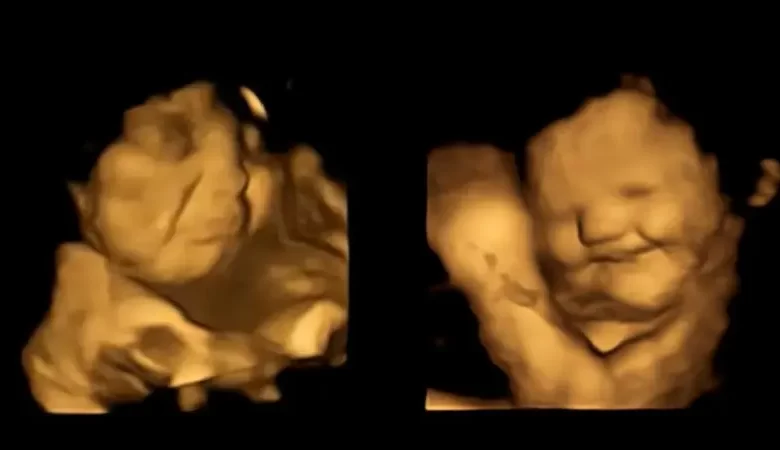

بحث علمي يفسر علاقة الطعام بضحك الجنين أو تكشيرته وهو برحم أمه

تلفزيون الفجر | تمكن علماء رصدوا وجوه الأجنة بموجات فوق صوتية، من التعرف إلى الحالة النفسية للأجنة وهم في أرحام أمهاتهم يتناولون الطعام لأول مرة، ووجدوا أن الجنين يبتسم حين يتذوق الجزر ويعبس تكشيرا عندما يكون اللفت هو الطعام، بحسب ما اتضح من تجارب خضعت لها 100 امرأة حامل، وابتلعت كل منهن كبسولة تحتوي على 400 ملليغرام من مسحوق الجزر أو الكرنب الملفوفي.

وبحسب ما بينت النتائج، فإن من تذوقوا نكهة الجزر اللطيفة أظهروا باستمرار استجابات أكثر “لوجه ضحوك” بعكس من تذوقوا الكرنب الملفوفي المر، حيث ظهر كل منهم بوجه عابس، لذلك ورد بالدراسة أن الكراهية الغريزية للطعم المر “هي منطقية من وجهة نظر تطورية، وهذا ما ساعد أسلافنا على تجنب السموم” لأن طعم معظمها منفر كرائحتها.

بالجزر يبتهج الجنين وبالكرنب الملفوفي ينزعج